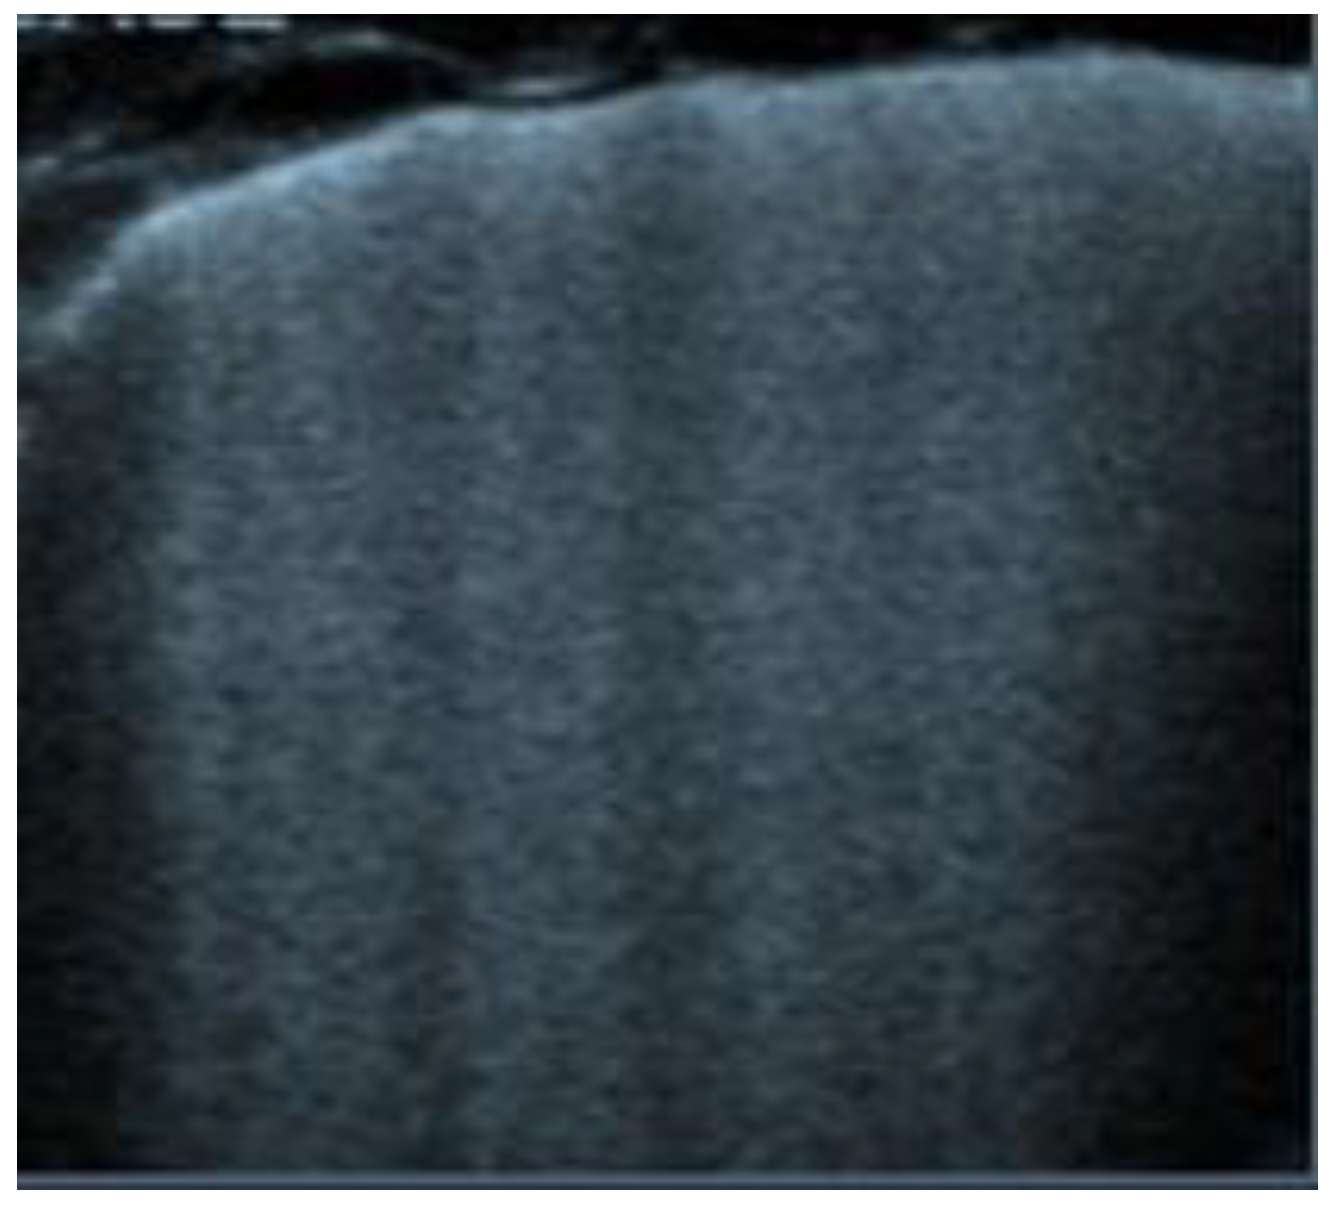

| B-Lines (Figure 4) | Vertical artifacts perpendicular to the pleural line | Presence of interstitial infiltrate, suggestive of acute pulmonary edema or COVID-19 pneumonia |

| Acute pulmonary edema | Presence of diffuse B-lines (Figure 9) |